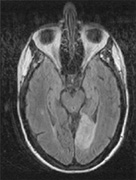

Fig. 18. Magnetic resonance imaging scan of patient with stroke causing a right hemiachromatopsia as well as partial superior quadrantanopia.

Achromatopsia in the contralateral hemifield alone can follow unilateral right or left occipital lesions (Fig. 18). Patients are typically asymptomatic until the defect is demonstrated on examination.234,235 Hemiachromatopsia is usually associated with a superior quadrantanopia;234,235,241 therefore, the color defect is only demonstrable in the remaining inferior quadrant. The preserved color vision in the ipsilateral hemifield allows normal or near-normal performance on centrally viewed tests of color vision such as pseudoisochromatic plates. The incidence of hemiachromatopsia is probably underestimated, given its asymptomatic nature and the failure of routine clinical color tests to detect its presence.

HEMIACHROMATOPSIA.